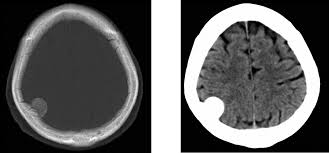

En este estudio, las mujeres que recibieron acetato de medroxiprogesterona de depósito presentaron un mayor riesgo relativo de diagnóstico posterior de meningioma, especialmente con exposiciones prolongadas e inicio de la medicación a edades más avanzadas. El elevado número necesario para producir daño sugiere un bajo riesgo clínico general. JAMA Neurology, 2 de septiembre de 2025.